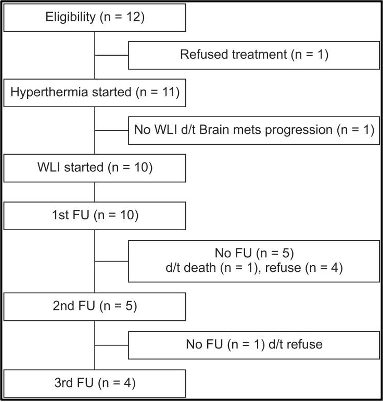

המחקר הסתיים מוקדם מכיוון שהצבירה הייתה נמוכה מהצפוי: 12 מטופלים הסכימו ונרשמו מנובמבר 2013 עד אוגוסט 2014. אחד סירב להמשך טיפול לפני הסימולציה ואחר לא קיבל הקרנה לאחר סימולציה בגלל התקדמות של גרורות במוח. מעקב היה זמין עבור 10 מטופלים לאחר חודש אחד, עבור חמישה מטופלים לאחר חודשיים, וארבעה מטופלים לאחר 3 חודשים בעקבות טיפול קרינתי לכל הכבד (WLI) עם היפרתרמיה (איור 1), וב-10 המטופלים שקיבלו טיפול קרינתי לכל הכבד (WLI) בוצעה אנליזה.

להלן איור 1: דיאגרמת סטנדרטים מאוחדים של ניסויים בדיווח (CONSORT)